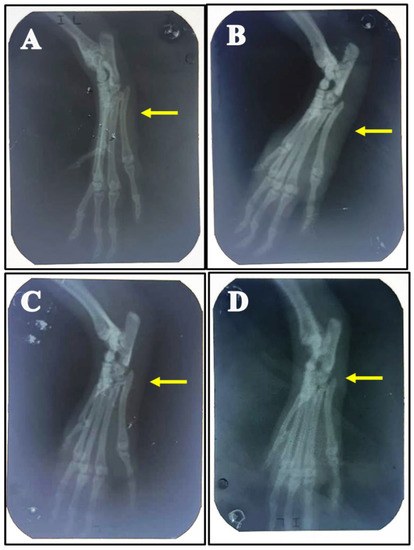

2.7. Radiographic Assessments

3.1. Effect of Stevia Extracts on the Edema of the Ankle Joint in Monosodium Urates Induced Gouty Arthritis